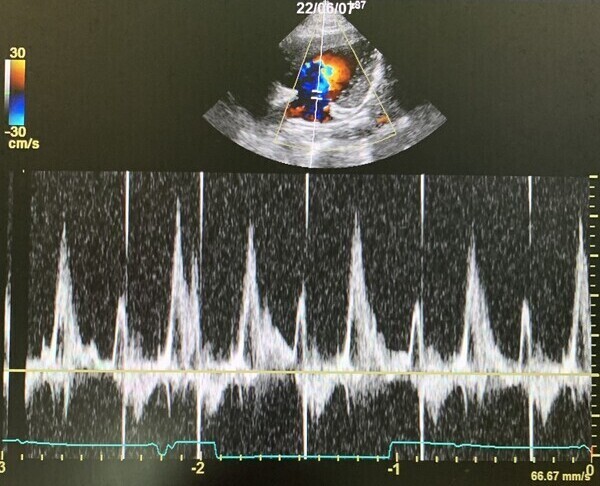

心臓病の検査で特に大きな要となるのが、超音波検査でありますが、大変高い技術が求められる検査であります。この技術により診断が左右することも大いにあります。当院では幅広い知識と高い技術で検査を行い、診断しております。この検査では、動物に横になったり、仰向けになったりしてもらいますが、その姿勢が苦手な子、またその姿勢によって息苦しくなってしまう子に対しては、立ったままの姿勢での検査を行っております。